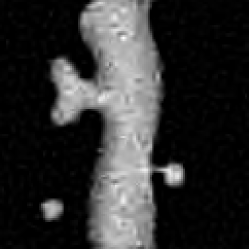

The same experiment as above was carried out with a microscopy image of the endothelial cell of the blood microvessel walls; see Fig. 2. For the NaiveGauss, AnsGauss and our approach, the dictionary ΦΦ\Phi contained the wavelet orthogonal basis and the curvelet tight frame. The AnsGauss and the NaiveGauss results are spoiled by artifacts and suffer from a loss of photometry. RL-TV result shows a good restoration of small isolated details but with a dominating staircase-like artifacts. RL-MRS and our approach give very similar results although an extra-effort could be made to better restore tiny details. The quantitative measures depicted in Fig. 3 confirm this qualitative discussion.

Fig. 2: Deconvolution of the cell image (Intensity \leqslant 30). (a) Original, (b) Blurred, (c) Blurred&noisy, (d) RL-TV, (e) NaiveGauss, (f) AnsGauss, (g) RL-MRS, (h) Our Algorithm.